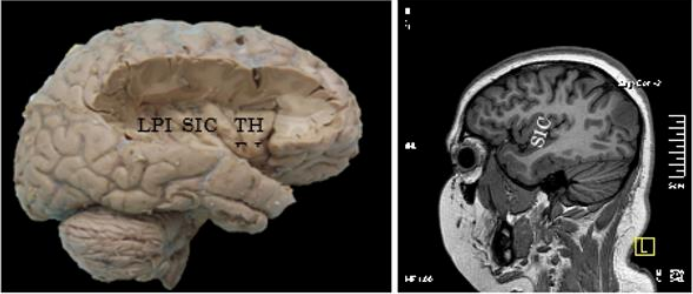

The insula contains a central insular sulcus (CIS), which divides it into two lobes: an anterior lobe (LAI), and a posterior lobe (LPI)1.

The SIC presented an average of 38mm in length, and its posterior sector was superficially topography at the level of the central or Rolandic sulcus.

The number of island gyres is variable, with a total of between 4 and 7 gyres. In our pieces we found: between 3 and 5 turns in the LAI (3-turn mode, in 12 cases); and between 1 and 3 turns in LPI (2-turn mode, in 12 cases) (figures 4 and 5).

Figure 4 and 5: anatomical preparation and MRI showing the SIC and insular gyri.